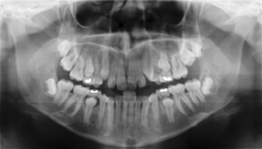

Utilising their Digital radiography, it is now possible to produce amazingly clear Radiographs (similar to the one below) within seconds of them being taken, using a much lower dosage of radiation than had previously been possible.